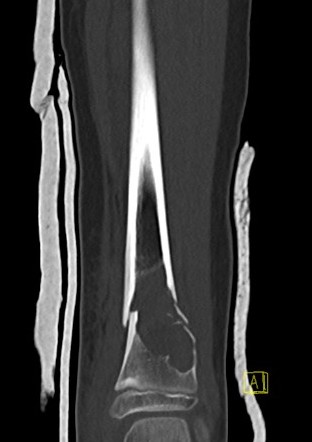

CT

X-ray

Well-defined lucency

- thin sclerotic rim

- usually central

- thinned cortex with slight expansion

- thin internal septa

- can be multi-loculated

Fallen-Leaf (AKA fallen-fragment)

- with pathological fracture

- indicates that the lesion has no matrix and is fluid filled

Fallen leaf sign